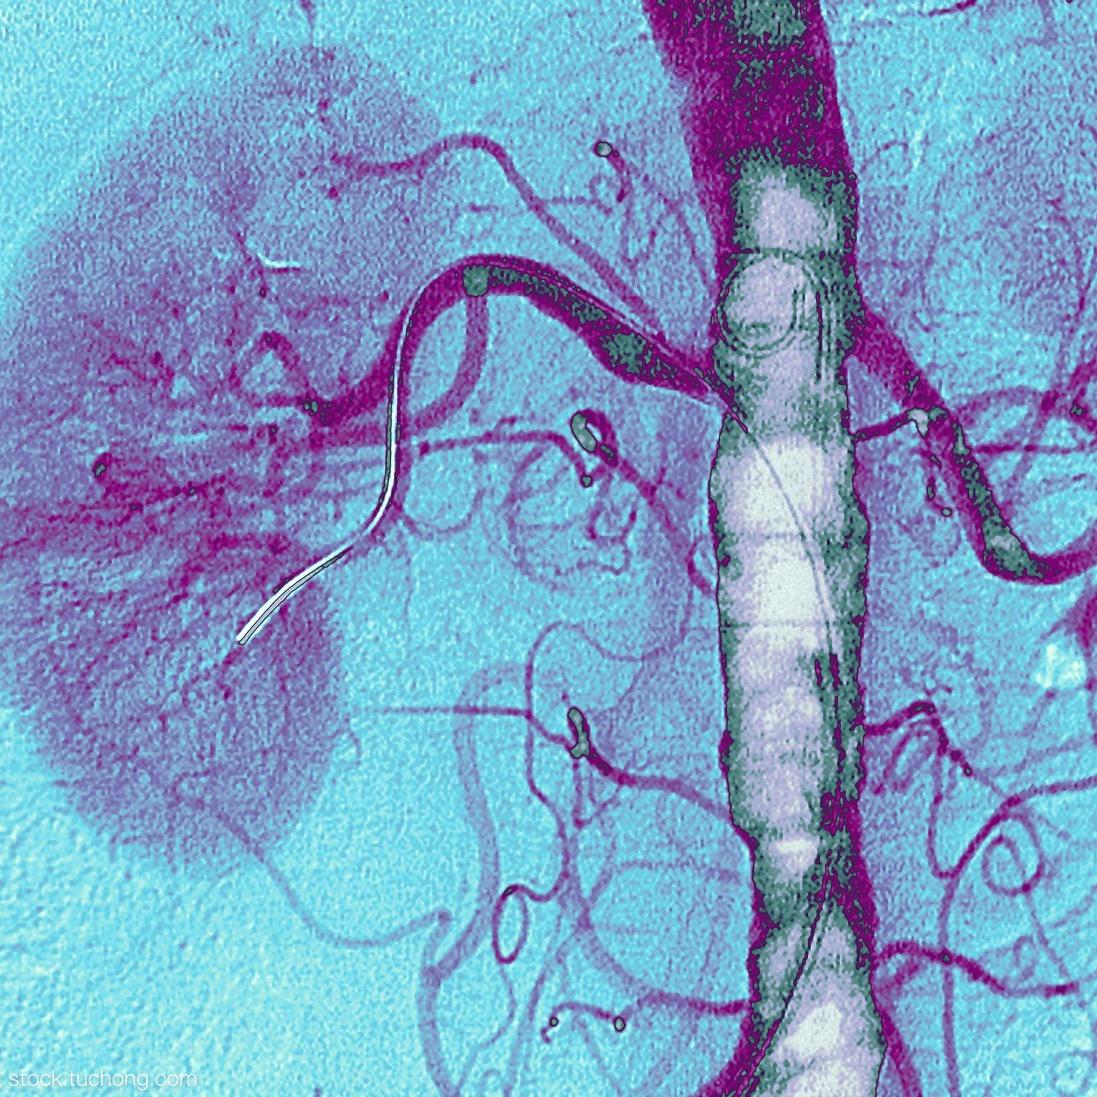

血管造影

一种 X 射线血管造影图像中多运动参数的分离估计方法